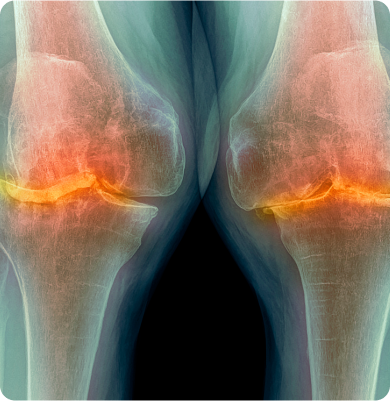

관절을 보호하는 연골이 노화, 반복된 사용 등으로 닳아 없어지며 통증과 염증을 유발하는 질환

노화로 인한 연골의 퇴행성 변화가 원인이며 비만, 반복적인 관절 사용, 외상, 유전적 요인 등도 발생에 영향을 줍니다.

무릎 관절 내 충격을 흡수하는 반달 모양의 연골인 반월상연골이 찢어진 질환

무릎이 회전하거나 갑자기 꺾이는 움직임 중에 반월상연골에 무리가 가면서 손상이 발생하며 스포츠 외상이나 노화로 인한 연골의 퇴행성 변화로 발생합니다.

무릎관절의 슬개골 아래 연골이 연해지고 손상되는 질환

슬개골에 반복적인 압력이 가해지거나 외상, 잘못된 자세, 근력 불균형 등으로 인해 연골에 손상이 생기며 발생합니다.

외부 충격이나 과도한 움직임으로 인해 무릎 관절의 인대가 늘어나거나 찢어지는 질환

주로 스포츠 활동 중 갑작스러운 방향 전환, 점프 착지, 외부 충격 등으로 발생합니다. 일상생활 중 무릎을 비트는 동작이나 넘어짐 등도 원인이 될 수 있습니다.

인공관절수술(전치환술, 부분치환술, 재치환술), 관절내시경 수술(미세천공술,연골성형술,자가골연골 이식술), 교정절골술, 반월상 연골판 절제술/봉합술, 인대재건술

골수 흡인 농축물 관절강내 주사(BMAC), PRP 관절강내 주사, 관절강내 연골주사치료, 물리치료